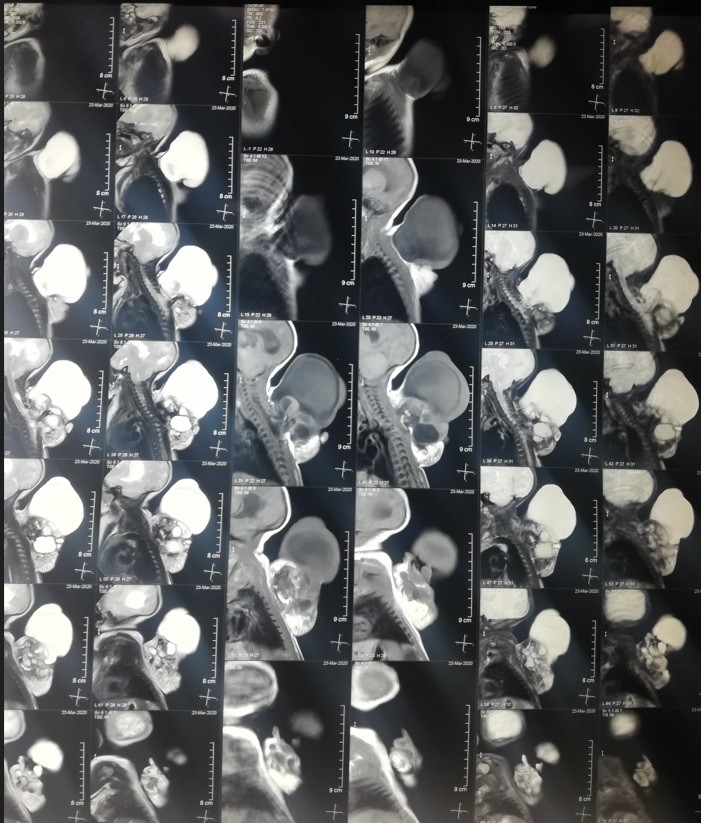

teratoma of the thoracic vertebrae in a newborn